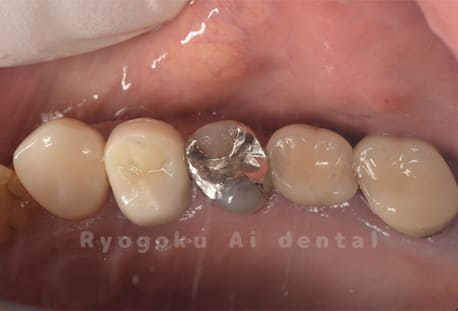

Case08

-

- 原因

- 虫歯

- 治療内容

- セラミックインレー

- 治療費用

- 77,000円

奥歯の黒い点が気になるということで来院された患者さんです。白い詰め物を外したところ、虫歯が中で大きく広がっていたため、患者さんと相談し、セラミックインレーで治療を行いました。

<リスク・副作用>

過度の咬合や衝撃で割れることがあります。